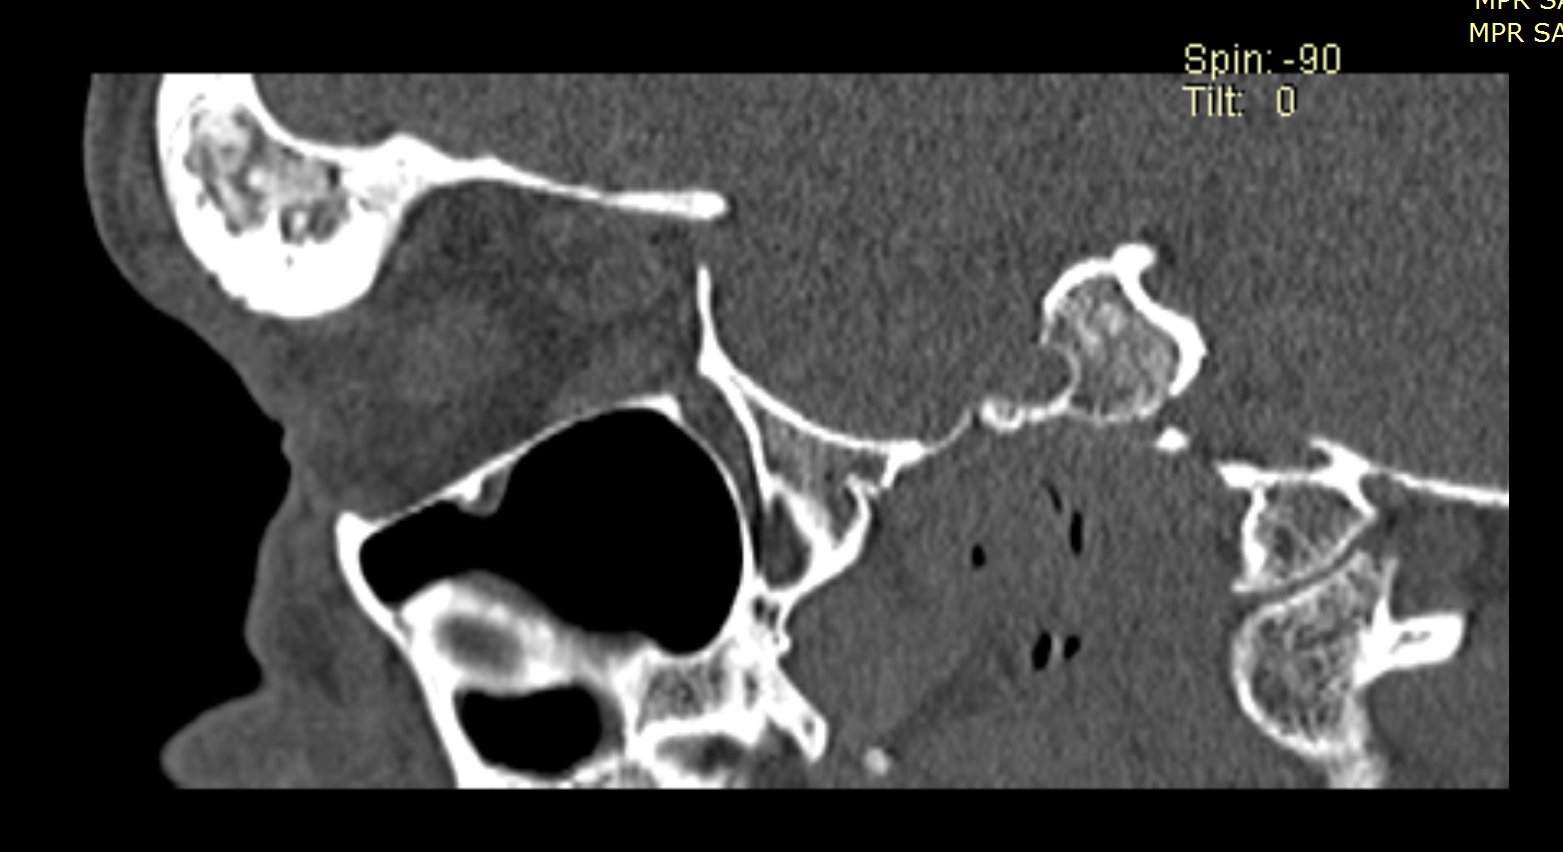

Ziua 1 postoperator, pacienta efectuează CT sinusuri paranazale de control care certifică ablația completă a formațiunii.